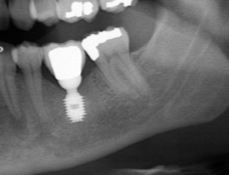

Так вот, чрезмерная атрофия альвеолярного гребня может лишить нас возможности имплантации — нам просто не хватит объемов костной ткани для нормальной установки имплантов. Однако, эта проблема решаема — существует целый ряд методик остеопластики (включая синуслифтинг), позволяющих восстановить любой объем костной ткани в в любом участке зубного ряда с высокой степенью эффективности. И, как правило, хорошие врачи в хороших клиниках так и поступают:

Увы, но подобные методики подходят не всем. Скажем так, я бы десять раз подумал прежде, чем проводить остеопластику пациенту, которому больше 80 лет, у которого есть серьезные проблемы со здоровьем. Также было бы сложно восстановить до необходимого полностью беззубый альвеолярный гребень со значительной атрофией по высоте:

Их можно установить в минимально возможный объем костной ткани, где установка обычных взрослых имплантов невозможна без предварительной остеопластики. В некоторых случаях они даже позволяют избежать синуслифтинга, что, согласитесь, звучит очень заманчиво.

Другими словами, уважаемые друзья, ультракороткие импланты призваны сделать нашу работу проще. Мы реально получаем шанс избежать сложной остеопластики, в некоторых случаях — открытого синуслифтинга, которым любят пугать некоторые фанаты с ультракороткими писюнами.